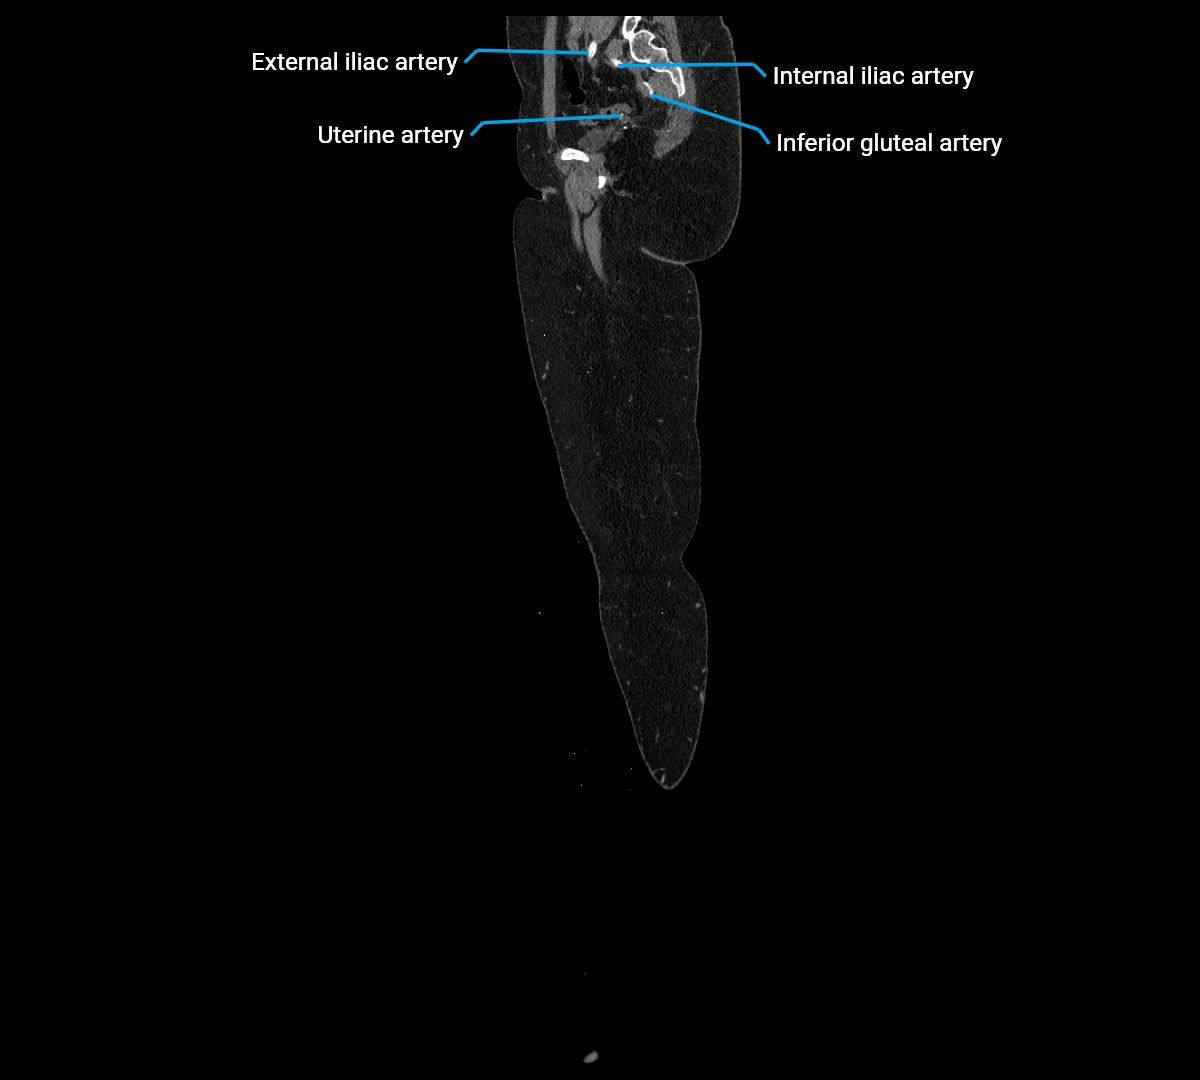

CT images

image

Contrast-enhanced CT (CTA):

• Gold standard for abdominal aortic imaging

• Provides excellent detail of lumen, wall, aneurysm, thrombus, and branch vessels

• Multiplanar and 3D reconstructions help in aneurysm measurement, stent graft planning, and dissection evaluation